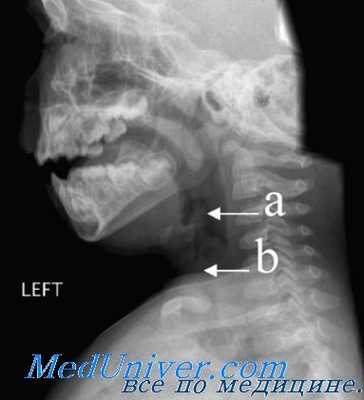

Некоторые особенности анатомического строения глотки могут изменить её резонаторную функцию. К числу этих особенностей относятся: а) короткое мягкое нёбо, б) очень глубокий свод верхнего отдела глотки.

а) На рисунке представлено короткое мягкое нёбо, которое во время сокращения поднимающих его мышц в целях разъединения носоглотки и ротоглотки, своим свободным краем касается слизистой оболочки глотки в области её свода, а не задней стенки, как это имеет место в норме. В формировании голоса главную роль играет не столько длина мягкого нёба, сколько его подвижность.

б) Аномалией в строении верхнего отдела глотки, изменяющей качество явления резонанса, принято считать чрезмерное углубление свода носоглотки.

При увеличении объёма верхнего отдела глотки в большом количестве возникают низкие тоны, придающие голосу тёмную окраску.